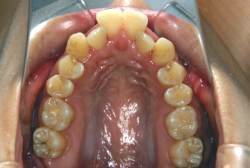

「隙間を閉じたい」という主訴で来院したケースです。診断の結果、「空隙歯列弓+軽度叢生」と判明しましたが、この方の場合は上は隙がある、つまりスペースが余っているのに対して、下は軽度の凸凹がある、つまりスペースが足りないと言う状態でした。

通常、凸凹の症状の場合は、小臼歯を抜歯させていただくのですが、この方の場合は凸凹も軽度で親知らずもないため、非抜歯で対応することになりました。マルチブラケット装置にて治療を開始し、治療期間は11ヶ月でした。治療後は正中の空隙が閉鎖されただけでなく、下の凸凹と下の歯並びの形態そのものが大幅に改善されました。もちろん噛み合わせ的にも正しい状態が確立しています。